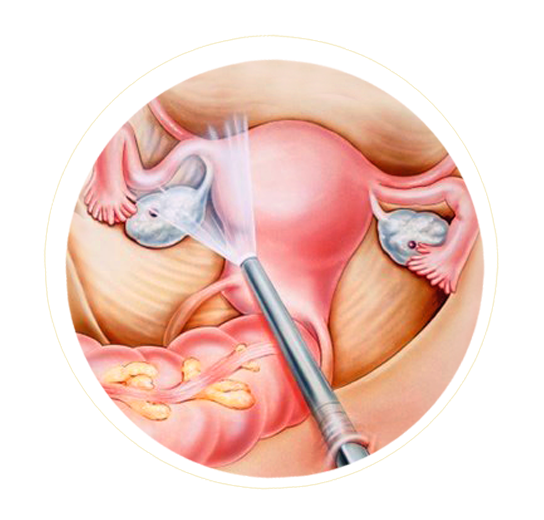

Our physicians are experts at minimally invasive surgical techniques. Minimally invasive surgical approaches emphasize small, limited incisions and surgical care as an outpatient. Our surgeons are skilled in advanced laparoscopic and hysteroscopic procedures.

Laparoscopic procedures can be performed using small incisions of around 0.5 to 1.5 cm that can be made far away from the surgical site.

Small, thin surgical instruments can then be passed through the incision and threaded through to the operational site.

The whole procedure is carried out using a laparoscope which is a small tube with a camera at the tip that can be used to relay images from inside the body to a TV monitor.